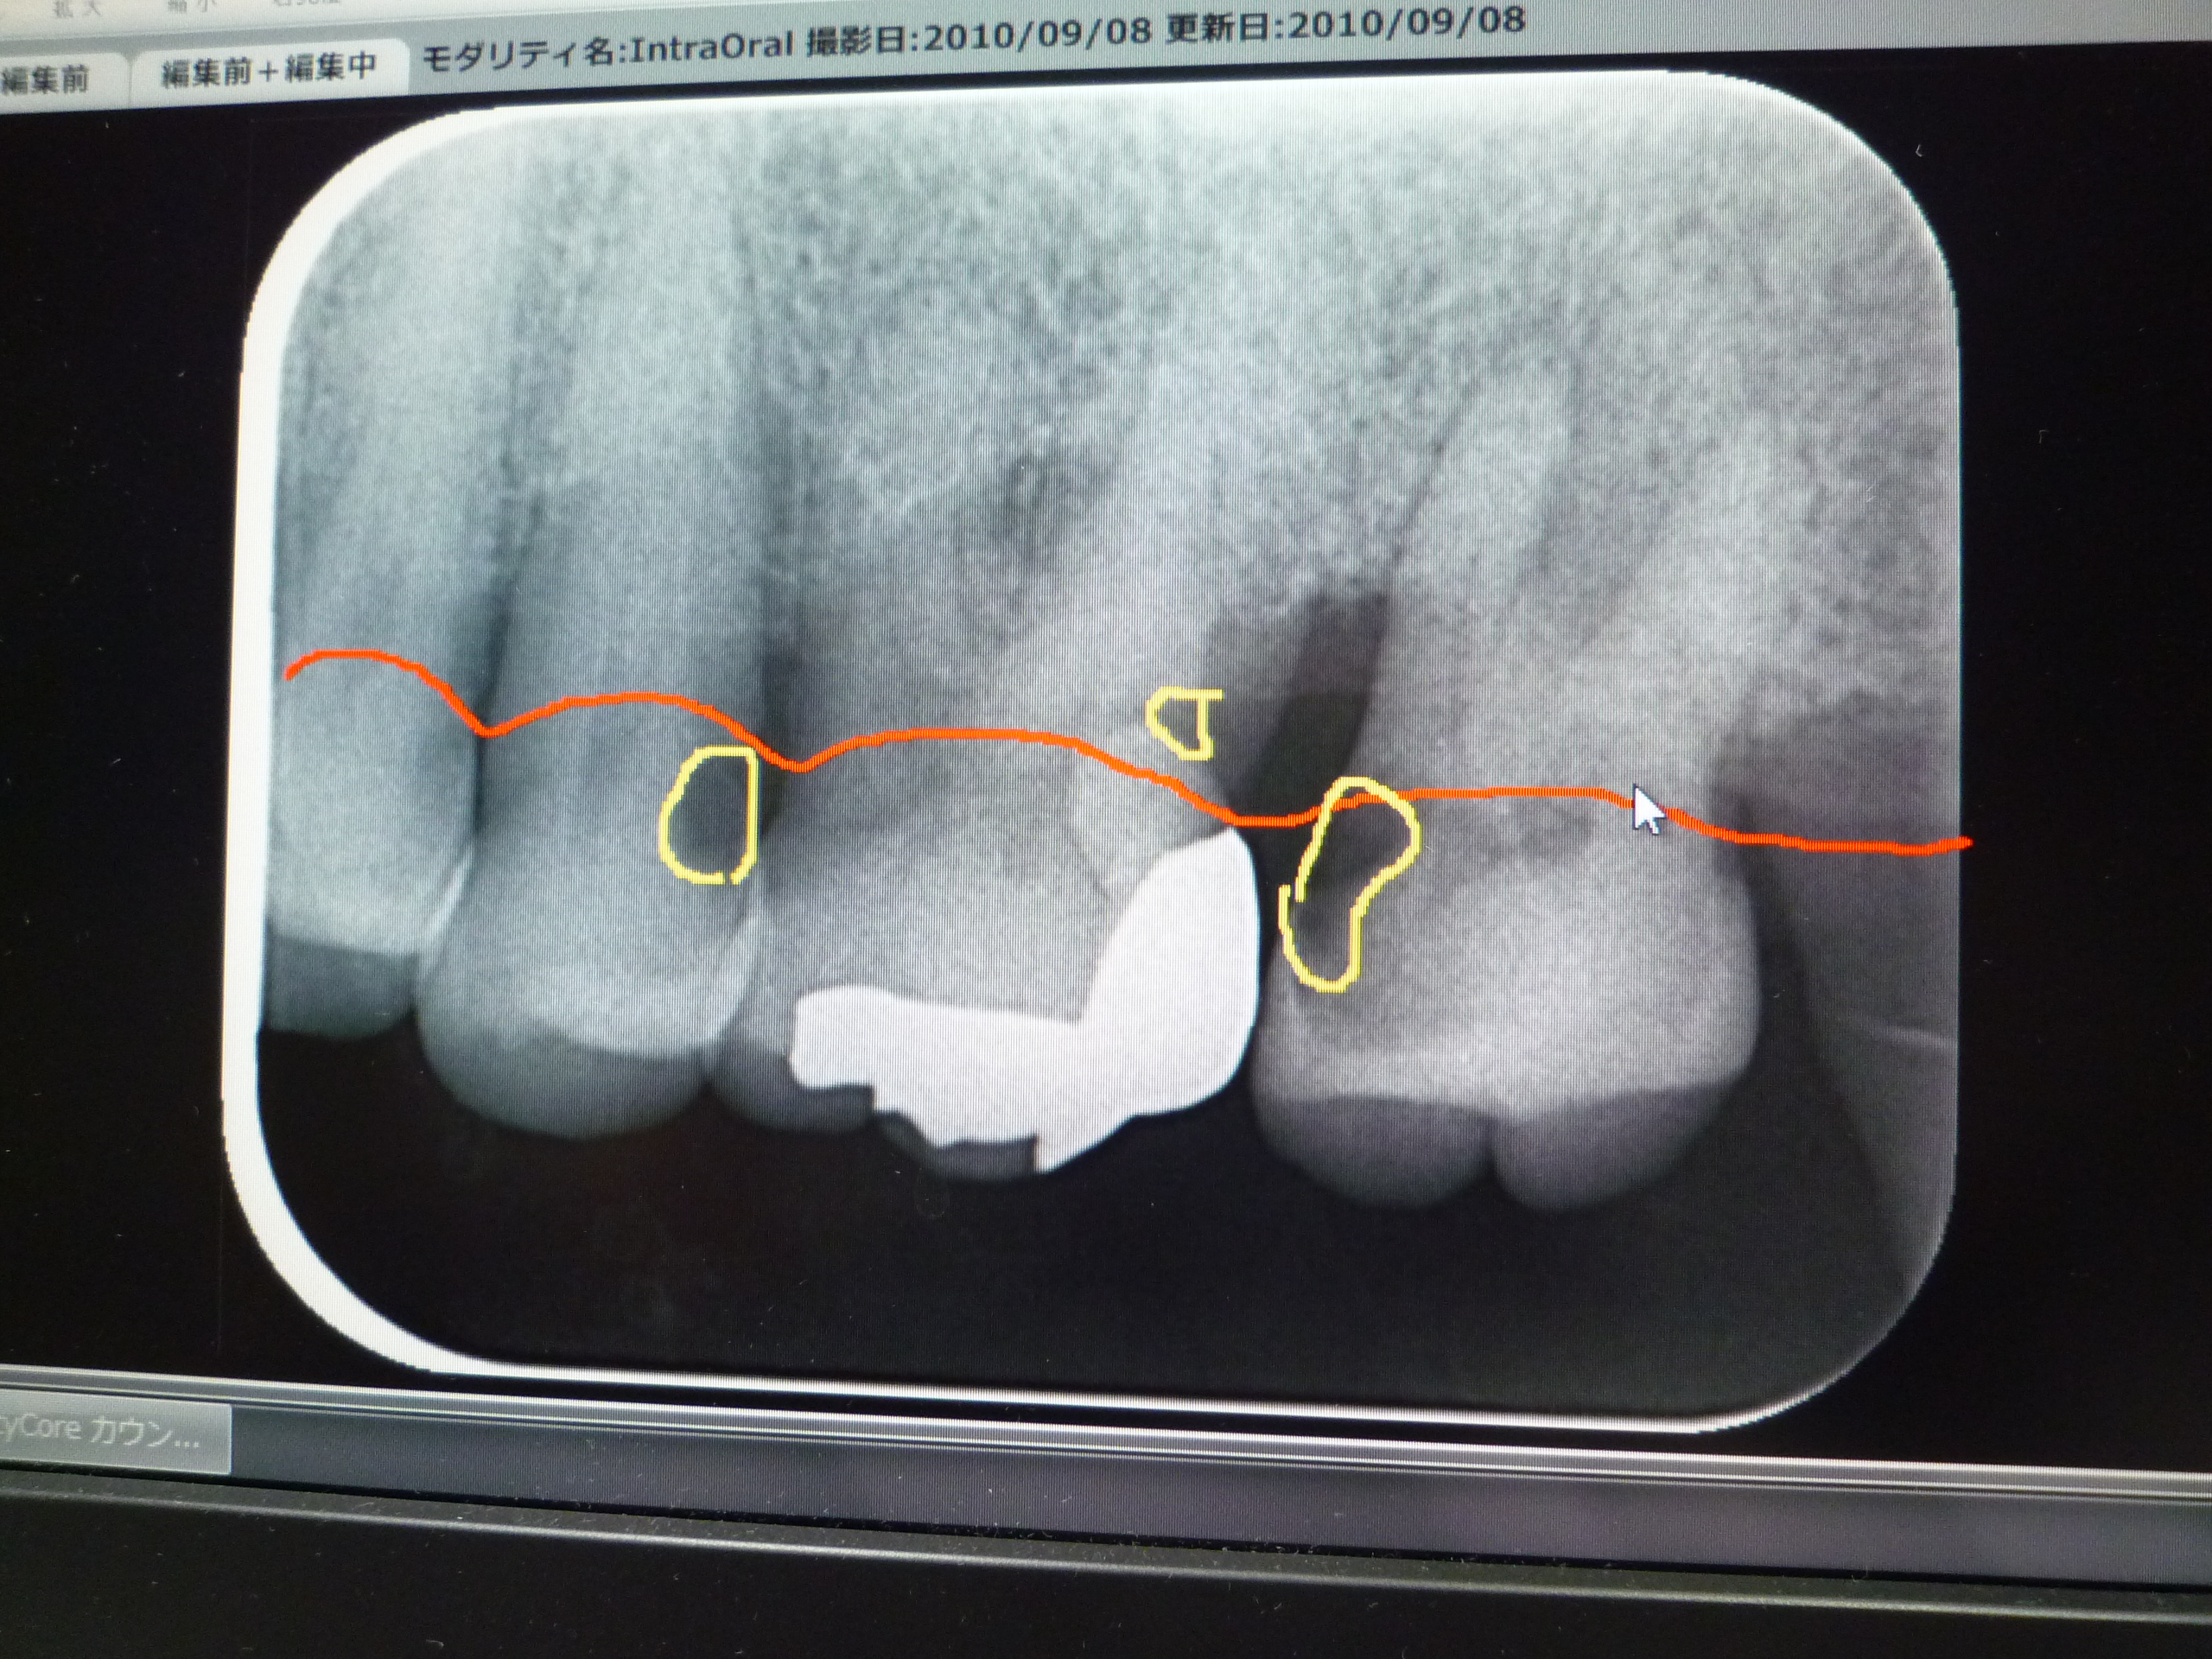

デジタルレントゲンについて

当院では「デジタルレントゲン」を使っています。メリットは、①放射線被曝が従来の1/4~1/16に軽減される、②撮影後すぐに見ることができる、などです。